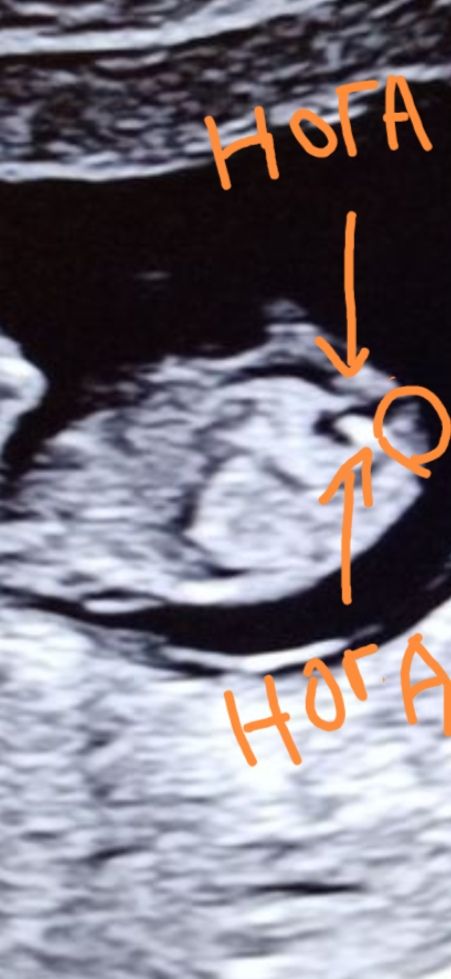

Полина Анисимова, а я думаю, что вот бугорок, в кружочке) Изображение

Юлия Sonnце, я тоже сейчас гуглила, ваш бугорок похож на бугорок))

Полина Анисимова, значит врач не уверена. Как говорят, хороший специалист никогда не скажет пол, если не уверен) а то знаете сколько таких случаев, устраивают гендер пати с одним полом, а рождается другой 🙈. И чаще всего ошибаются с девочками. В общем из девочек чаще может вырасти мальчик, чем наоборот) Мне вот на первом скрининге сказали 100% мальчик, но я решила подождать второго скрининга ( хоть тут кружочек и закрасила) ещё неделька )))